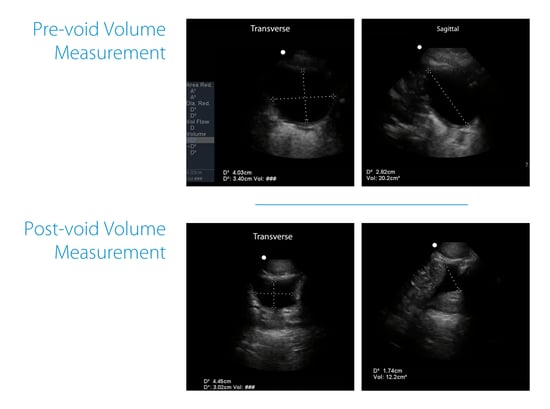

Example from training:

Pre-void volume measured about 20.2 cc.

After the patient attempted to void, repeating the same steps produced a post-void residual of about 12.2 cc.